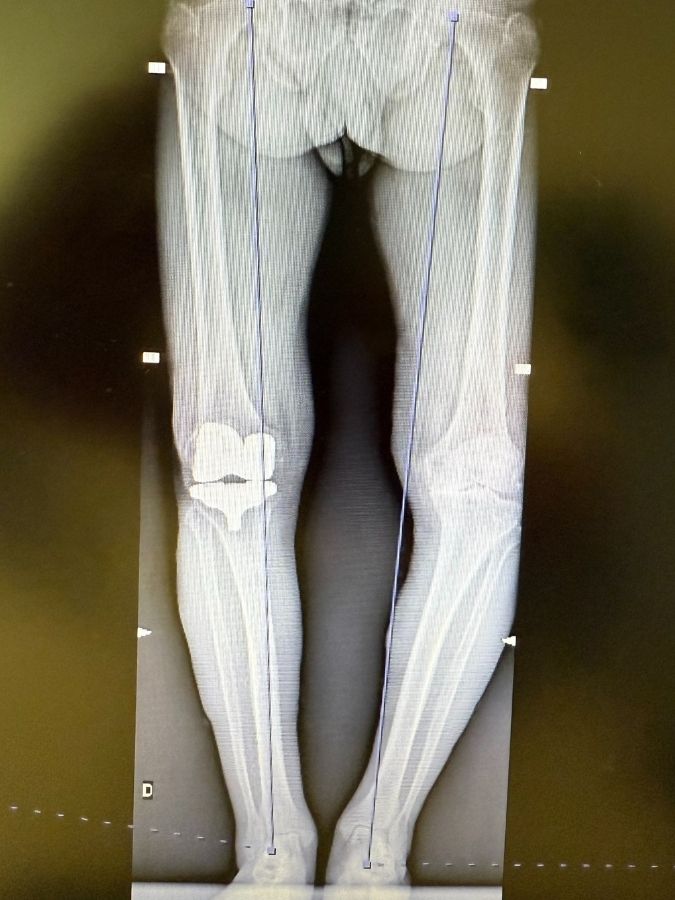

In alcuni pazienti, le condizioni cliniche dell’articolazione e le limitazioni funzionali associate rendono necessario il ricorso all’intervento chirurgico per SOSTITUIRE L’ARTICOLAZIONE USURATA con una protesi. La protesizzazione è un intervento di RIVESTIMENTO: “sbucciamo” la parte malata e la “rivestiamo” con leghe di metalli e polietilene ripristinando lo stesso spessore asportato (al netto dell’usura).

• Con la protesi monocompartimentale (parziale) viene sostituito solo il compartimento del ginocchio danneggiato dall’artrosi.

• Con la protesi di ginocchio totale viene sostituita l’intera articolazione (normalmente in Europa non si sotituisce la rotula)

Protesi Monocompartimentale

Protesi Totale

Nel 2016 ho iniziato a utilizzare la tecnica dell’ALLINEAMENTO CINEMATICO, seconda esperienza in Europa (qualche mese prima l’aveva fatto il mio amico Callies ad Hannover) e prima in Italia. È stata la GRANDE RIVOLUZIONE dell’Ortopedia del Ginocchio mondiale. Le protesi andavano bene solo nel 75% dei casi, oggi nel 97%!!!

Prevede la ricostruzione dell’asse nativo dell’arto del paziente: non abbiamo gambe tutte uguali e col tempo e l’usura si storgono. Con questa tecnica rimettiamo l’arto come era a 20anni e, rispetto alla tecnica vecchia, rispettiamo i tessuti del ginocchio. Quando si sfiammeranno (ci vuole un anno ddall’intervento!!!), non riconosceranno più la protesi come qualcosa di estraneo.

Inoltre nel 2016 ho pensato di utilizzare una PROTESI ANATOMICA, molto simile alle ginocchia nel loro interno (quasi uguali, tranne le dimensioni, per tutti noi) associata alla tecnica dell’allineamento cinematico. Questo mi consente di offrire una personalizzazione della protesizzazione ricreando la cinematica articolare specifica per ogni persona, senza ledere i legamenti. Una grande felicità per me è stata che l’inventore dell’allineamento cinematico, il mio amico e mentore Stephen Howell, dal 2018 abbia parimenti deciso di associare alla tecnica la stessa protesica anatomica che avevo cominciato ad utilizzare 2 anni prima.